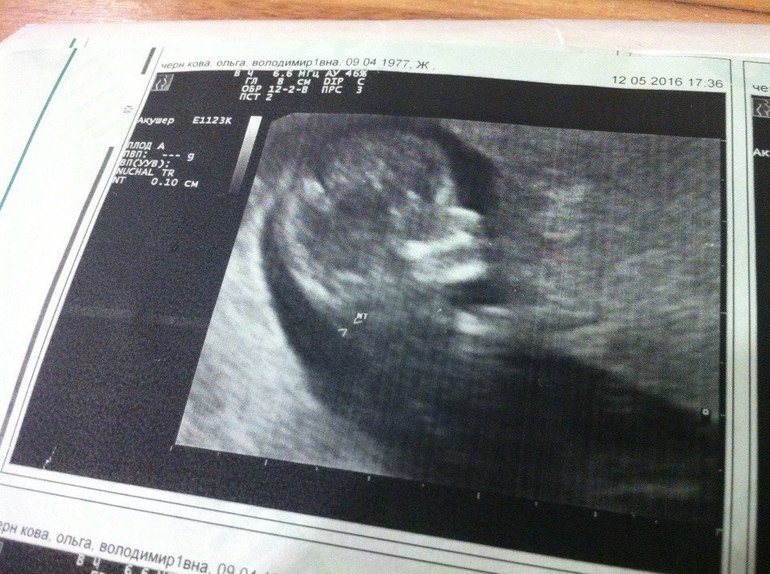

Мы на аналогичном сроке)) КТР 43.1 ...у нас мальчик)) 12.05 когда делали УЗИ было 11,4 по месячным. Но мы опережаем по УЗИ с первых дней на недельку.

Здорово!! У меня у сына тоже в 12 недель что-то торчало, у дочки не торчало ))) и сердечко к сына было 145 , а у дочки больше ) Крепкого здоровья вам и малышу🙏🏻

Объясните, пожалуйста, торчит там, где крестик справа? Вижу фаберже, но крестик мешает)